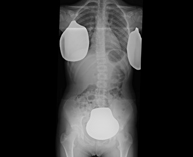

- Abdomen X-ray

An abdominal X-ray uses a small dose of radiation to obtain a two-dimensional image of the abdomen with its anatomical structures (stomach, small intestine, large intestine, liver, pancreas, kidneys, bladder, bony pelvis, etc.).

- Spinal teleradiology

This technique uses X-ray rendered imaging to examine the entire spinal column, especially assessing the presence of scoliosis and pelvic dysmetria.